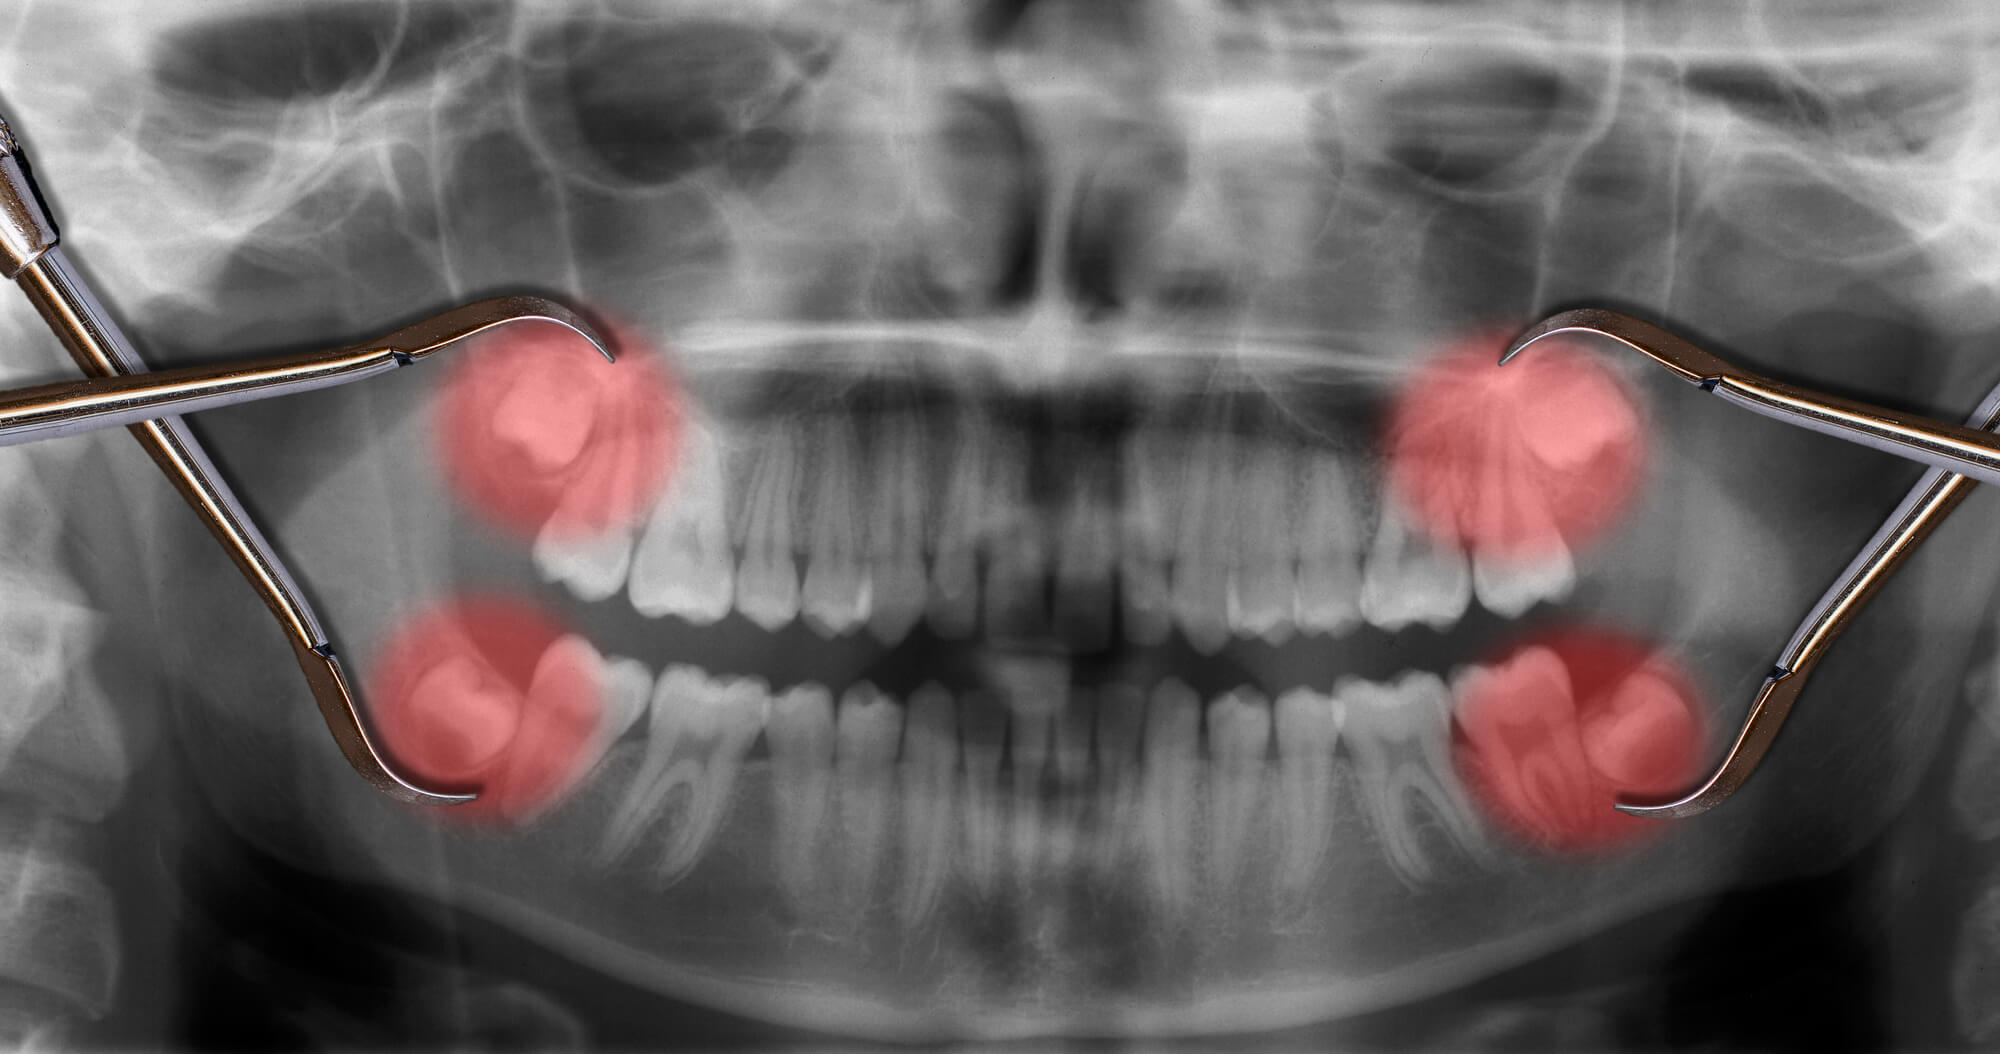

A tooth becomes impacted when there is not enough room to accommodate the space in the dental arch and growth becomes impossible. After surgery to remove an impacted tooth, mild discomfort and some swelling is expected. This is part of the process and should not alarm you. You may use cold compresses to alleviate the swelling. In addition, your doctor will prescribe pain medication, which should be taken as directed. Patients are also advised to favor the extraction area and modify their diet for a few days to allow for healing.